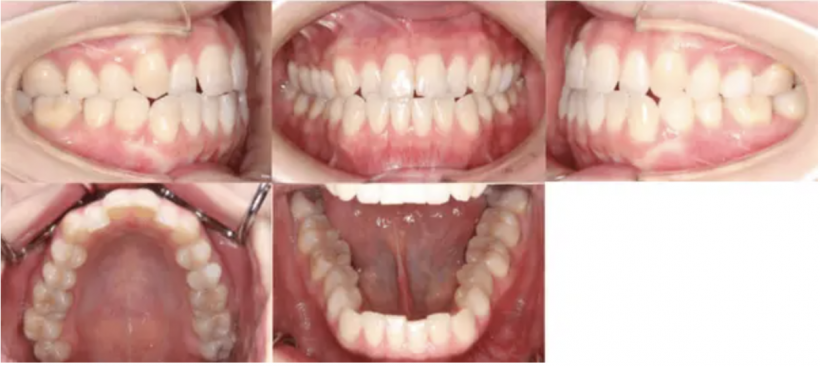

治療例②部分矯正: 23歳

【治療前】

【治療後】